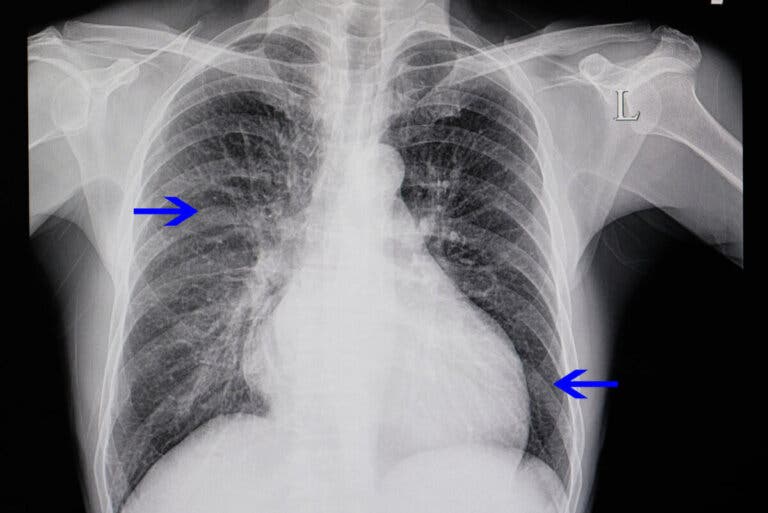

El término cardiomegalia significa aumento del tamaño del corazón. Con frecuencia, un corazón agrandado es un hallazgo en una radiografía de tórax que se realizó por otra razón.

Como se mencionó antes, a veces aparece como un hallazgo en un estudio de imagen solicitado por otra razón. Un ejemplo es cuando el médico indica una radiografía de tórax para observar los pulmones y aparece un corazón agrandado.

- Radiografía de tórax: con esta técnica se puede ver el estado de los pulmones y el tamaño del corazón. Si aparece dilatado en una radiografía se necesitarán otras pruebas.